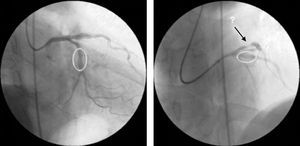

Ad-hoc angioplasty was performed on both vessels with direct stenting (Fig. 2), using standard intracoronary devices (3.0mm×12mm in the proximal LAD and 3.0mm×15mm in the circumflex artery).

Angiographic control of the last lesion treated (proximal LAD) showed a good angiographic result at the stent implantation site, but a new pre-stent lesion was now visible in the proximal circumflex artery (Fig. 3).